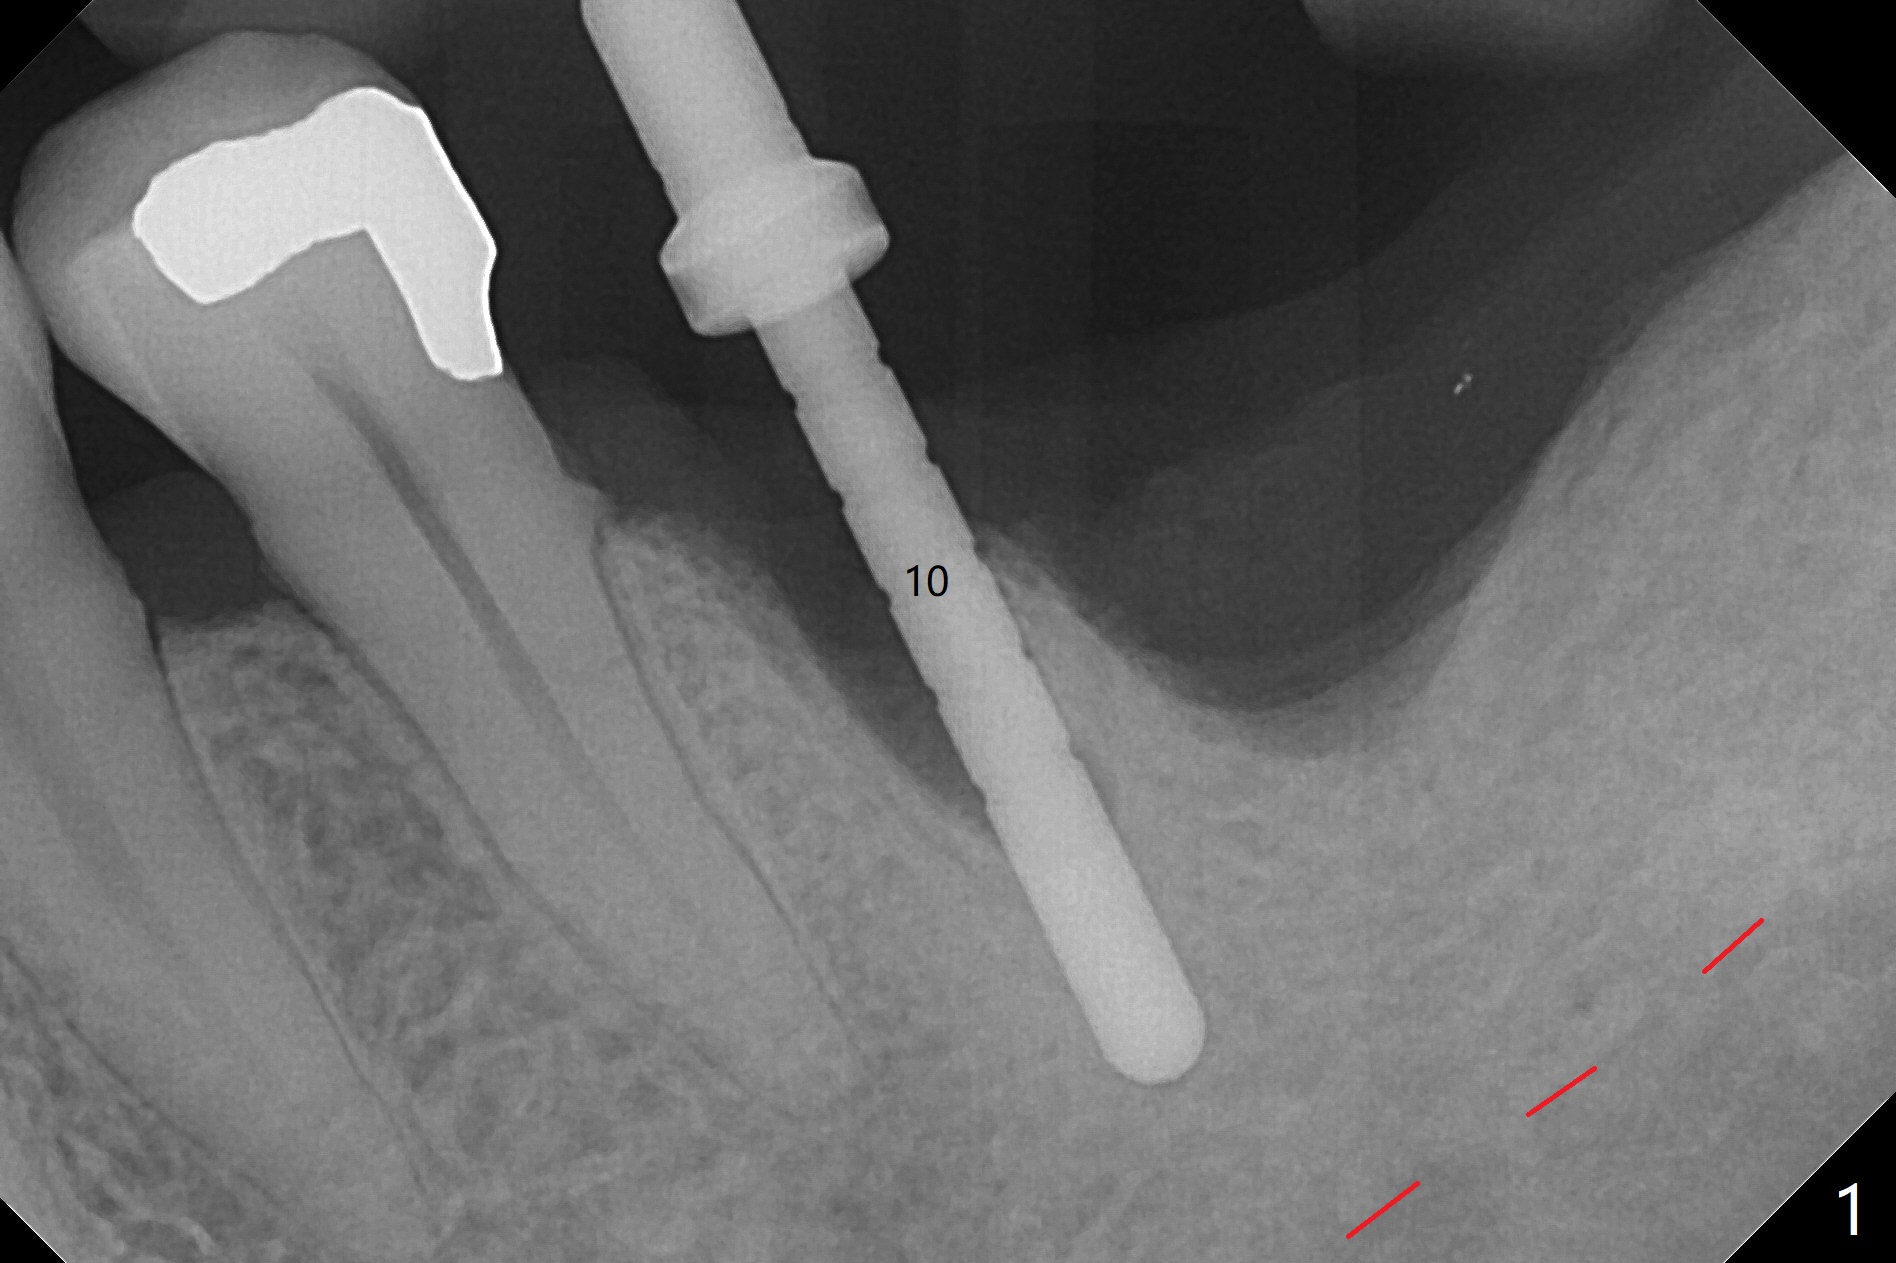

The guide does not arrive when the tooth #19 is extracted. Osteotomy is initiated free hand in the mesial socket as planned, slightly lingual, for 11.5 mm (Fig.1). Following sequential osteotomy, a 4.5x10 mm implant is placed subcrestal septally (Fig.2 S) and 2.3 mm from the neighboring apex (Fig.4). A 5.5x5(4) mm abutment is placed immediately and allograft is placed in the remaining sockets (Fig.4 *). An immediate provisional is fabricated to keep the graft in place (Fig.5 P; the most secure socket preservation).